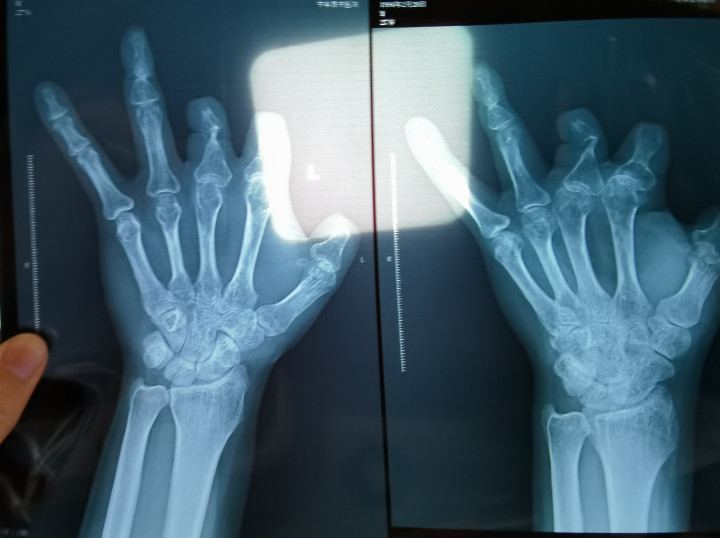

患者王海森左手拇指关节以上部位被电锯切断,收费单显示术中使用了微血管吻合装置,但X光片中未显示该器械。新京报记者程亚龙摄

该产品的代理商曾向新京报记者证实,微血管吻合装置为植入型医疗器材,患者拍摄X光片时会有显示。新京报记者获取了一位曾在郑大一附院接受手术、使用了该产品的患者的X光片,其手术部位可见一绿豆大小的光圈。

王海森称,他出院约1年后,有人曾找到他说,这个价格昂贵的进口器材,并没有在手术中使用。当时他没有相信,直到2021年12月,BG真人(BigGaming)官方网站经人提醒,王海森在老家开封尉氏县人民医院拍摄了左手X光片,才确认手术部位的确没有微血管吻合装置。2021年12月底,王海森向郑州市公安局二七分局刑侦大队报案。

2021年12月,患者彭先生拍摄的左手X光片,未见收费单据中列出的微血管吻合装置。新京报记者程亚龙摄